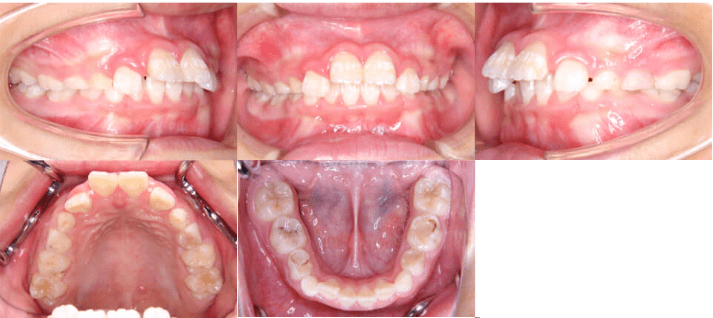

治療前

• 初診時年齢:8歳5ヶ月

• 主訴:上の前歯がでていて口が閉じづらい

• 診断:過大なオーバージェットを伴う過蓋咬合症例

• 抜歯箇所:非抜歯

• 治療内容:マウスピース型カスタムメイド矯正歯科装置(製品名インビザライン 完成物薬機法対象外)を使用して主訴である上の前歯の突出を改善しつつ、前歯のかみ合わせが深い過蓋咬合についても下の前歯を押し下げて上あごの歯ぐきを噛まなくなるように改善しました。

• 治療期間:10ヶ月

• リスク:矯正治療による歯の移動に伴う痛み、歯根吸収、虫歯

• 費用:44万円